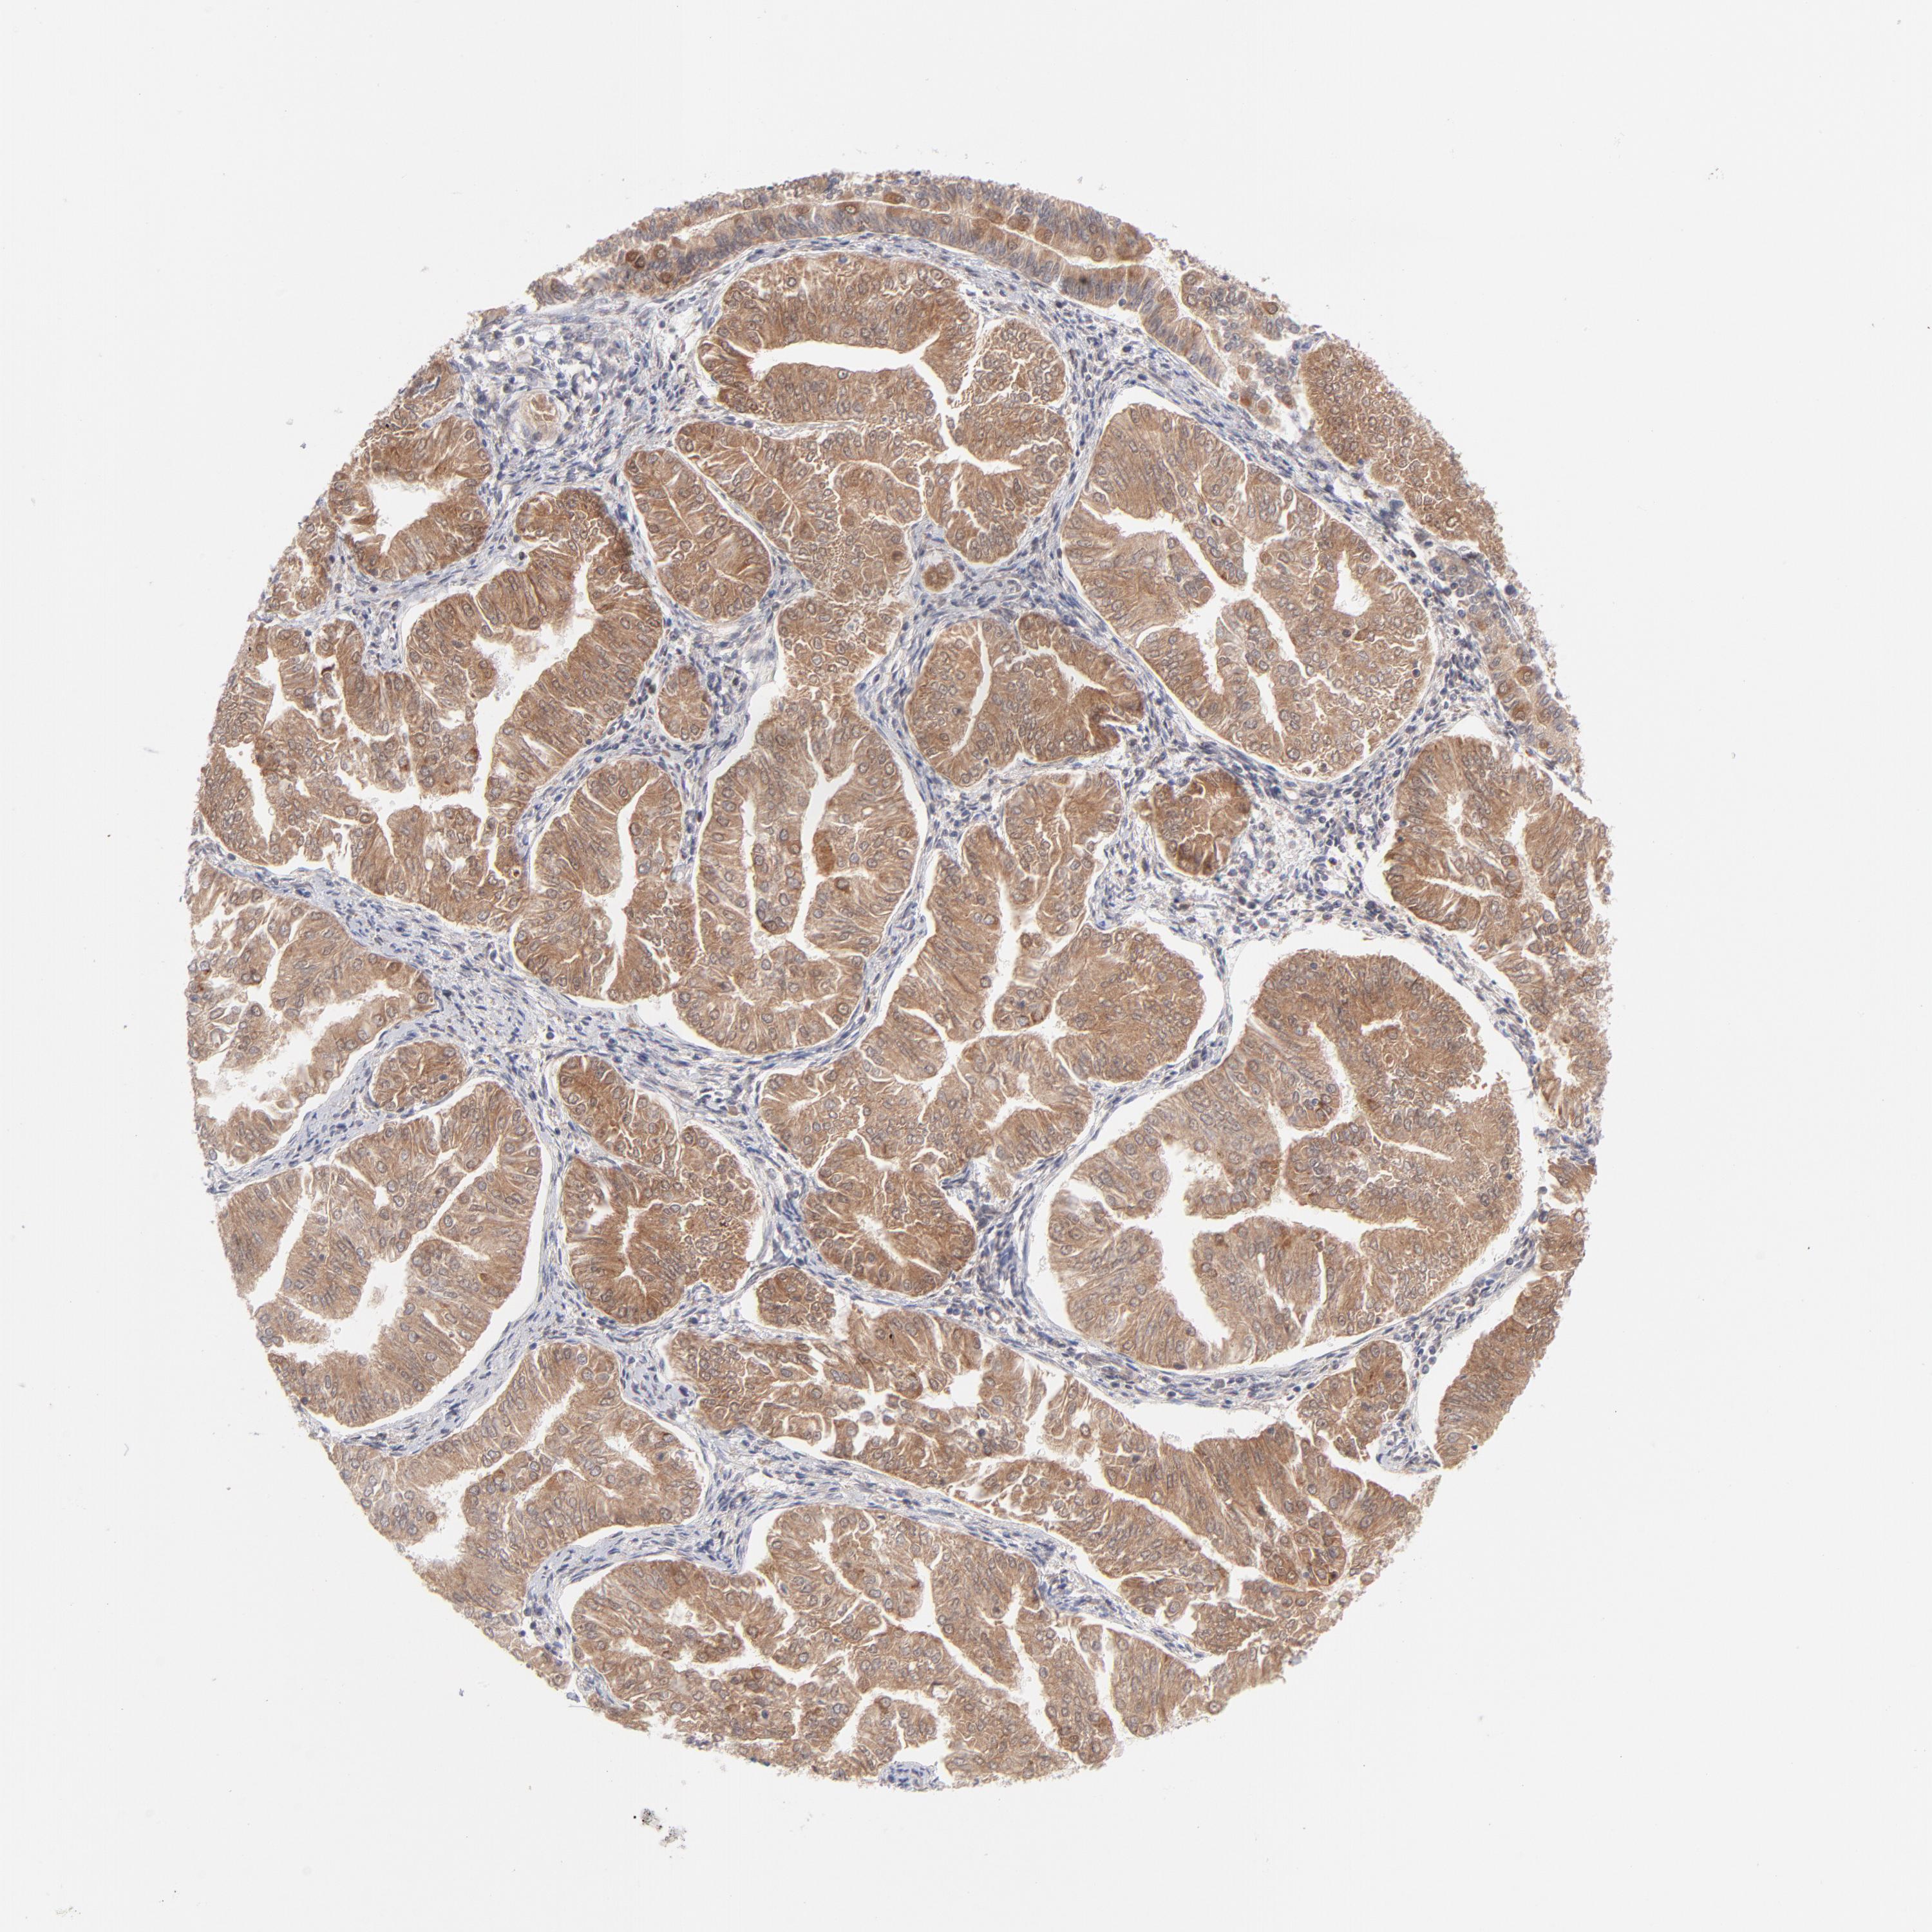

ENDOMETRIAL CANCER - Protein expressioni

A mouse-over function shows sample information and annotation data. Click on an image to view it in a full screen mode. Samples can be filtered based on level of antibody staining by selecting one or several of the following categories: high, medium, low and not detected. The assay and annotation is described here.

Note that samples used for immunohistochemistry by the Human Protein Atlas do not correspond to samples in the TCGA dataset.

Antibody stainingi

Antibody staining in the annotated cell types in the current human tissue is reported as not detected, low, medium, or high, based on conventional immunohistochemistry profiling in selected tissues. This score is based on the combination of the staining intensity and fraction of stained cells.

Each image is clickable and will lead to virtual microscopy that enables deeper exploration of all samples and also displays staining intensity scores, fraction scores and subcellular localization as well as patient and tissue information for each sample.

Antibody HPA003628

Staining

High

Medium

Low

Not detected

Intensity

Strong

Moderate

Weak

Negative

Quantity

>75%

75%-25%

<25%

None

Location

Nuclear

Cytoplasmic/membranous

Cytoplasmic/membranous,nuclear